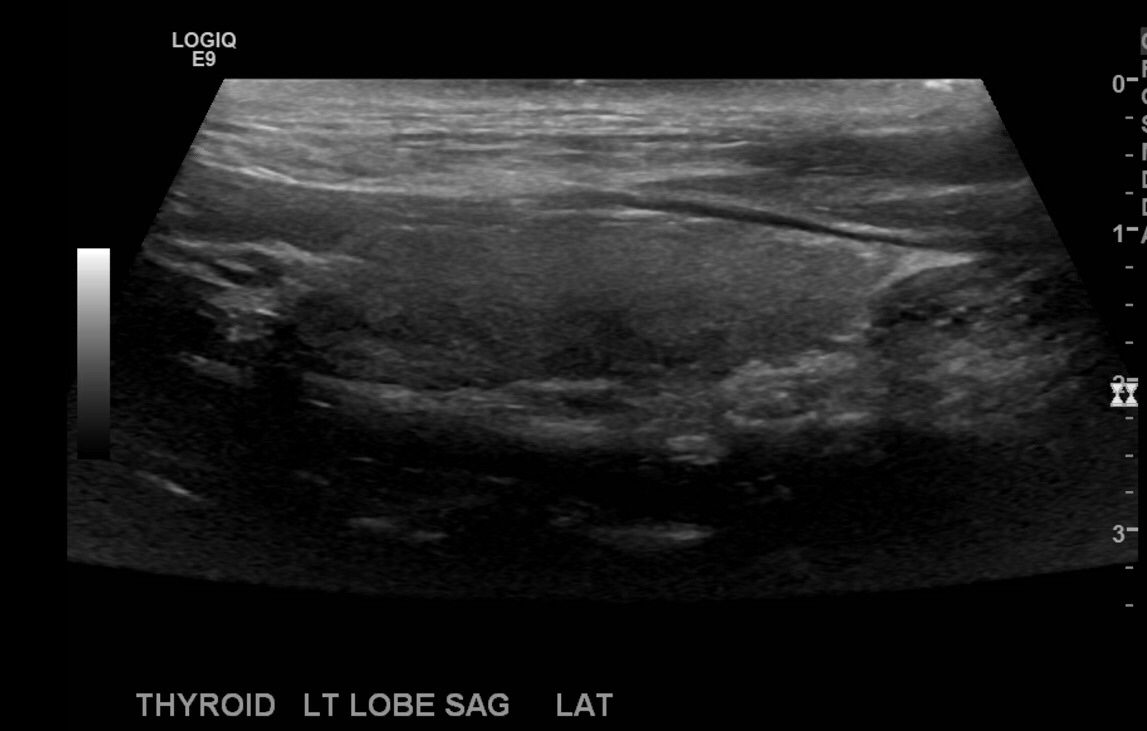

Repeat the process on the left.

Go to the right neck and take sagittal images in middle of the right thyroid lobe, lateral and medial.